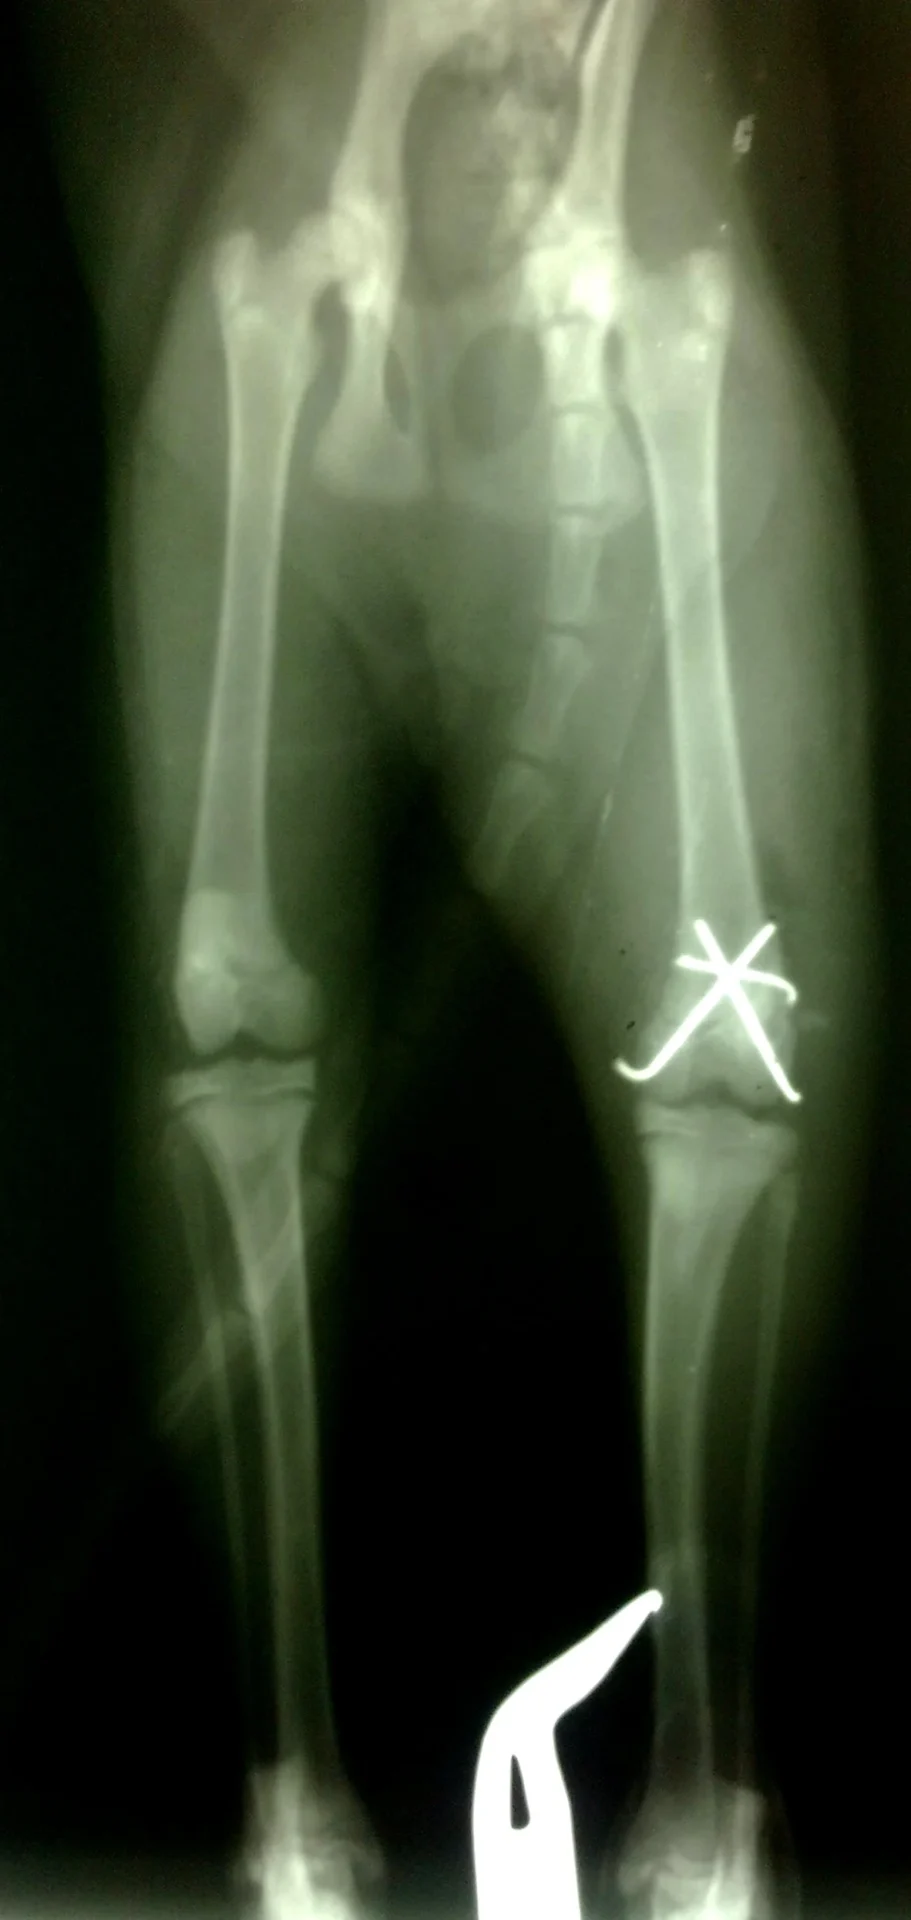

Galería de casos clínicos

Casos clínicos de cirugía (tejidos blandos, traumatología, neurocirugía, artroscopia)